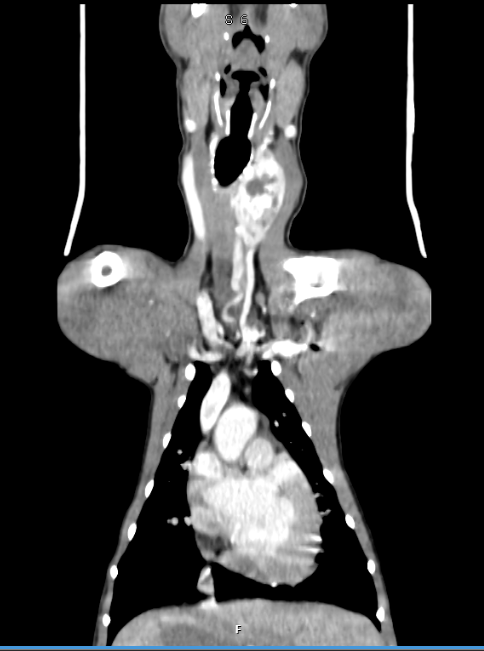

A CT scan showing the tumour on little Lenny's neck

“The next step was to explore if the growth was operable so our specialist diagnostic imaging service performed an advanced CT scan to establish whether surgery could be performed.

“LVS is one of only a handful of specialist centres to have this advanced imaging option in central London and it was very important in this case.

“The CT images pinpointed the large growth within the left thyroid gland in Lenny’s neck and we were confident we could operate successfully and significantly increase the length and quality of his life.”